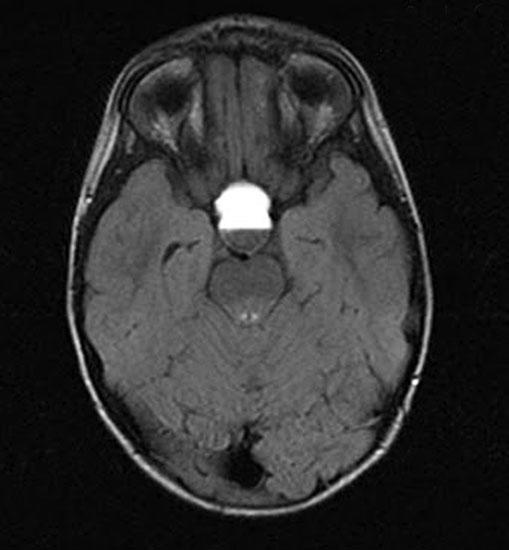

Основная роль в диагностике опухолей головного мозга, в том числе и краниофарингиомы, отводится компьютерной томографии и магнитно-резонансной томографии. Оба эти метода позволяют врачу получить послойное изображение тканей мозга, в результате чего возможно оценить локализацию опухоли, ее форму, размеры и структуру, а также отношение к соседним тканям. КТ и МРТ - неинвазивные методы диагностики, при этом КТ основан на рентгеновском излучении, а в МРТ используется мощное электромагнитное поле.